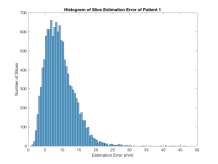

We have tested our approach on 85 randomly selected and accurately segmented healthy adult brains, on a real-world use case scenario with 34 roughly delineated fetal brain MRI scans and on 60 low-dose thorax CT scans with no organ specific segmentation. SVRNet’s average prediction error for these datasets is respectively 5.61.07mm, 7.74.80mm, and 5.92.43mm. We evaluate 3D reconstruction performance using the Peak Signal-to-Noise Ratio (PSNR) and prediction error as average distance in mm between ground truth locations and predicted locations , i.e., .

Exp. 1: Segmented adult brain data is used to evaluate our network’s regression performance with known ground truth . 85 brains from the ADNI data set[1] were randomly selected; 70 brains for and 15 brains for . Fig. 2 shows an example slice of the ground truth and the reconstructed .

Each brain has been centered and re-sampled in a volume. Using the Fibonacci Sphere Sampling method, a density of 500 unique normals is chosen with 64 sampling planes spaced evenly apart on the Z-axis (giving a spacing of 4mm). This therefore yields a maximum of 32000 images per brain; 2.24M for the entire training set and 345K for the entire validation set. After pruning with little or no content, this figure drops to approximately 1.2M images for training and 254K for validation. Training took approximately 27hrs for 30 epochs.

Reconstructing from initialisation without SVR yields a PSNR of 23.7 1.09; with subsequent SVR the PSNR increases to 29.52.43 when tested on 15 randomly selected test volumes after four iterations of SVR.